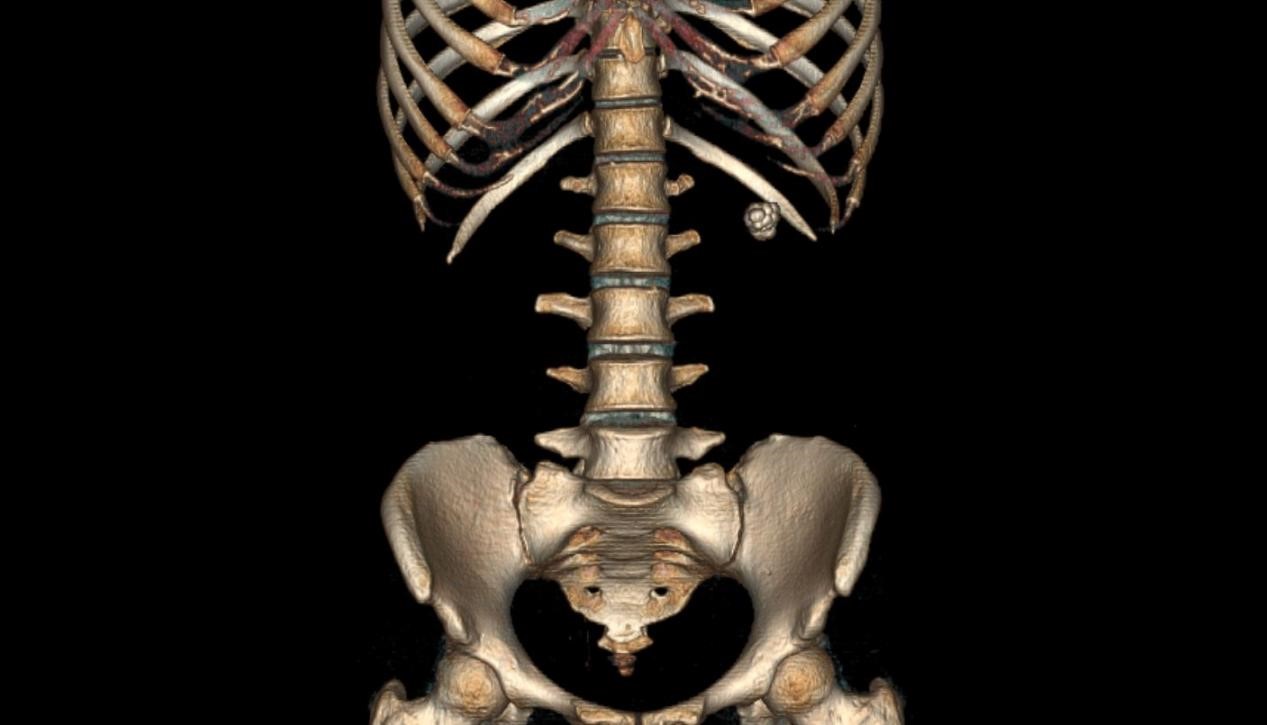

肾盏憩室结石是一种泌尿系统疾病,通常发生在肾脏的憩室内。憩室指的是肾脏皮质或肾盏的局部膨出,形成的小型囊状结构。其内因尿液滞留,容易形成结石。这类结石可能引发肾绞痛、尿路感染甚至肾功能损害。临床表现常为腰痛、尿频、尿急等症状,若结石较大,可能导致尿路梗阻。影像学检查如CT或超声可帮助诊断。在治疗方法上主要包括药物治疗、体外冲击波碎石及手术治疗等。在日常生活中,保持充足的水分摄入,预防尿液浓缩,有助于降低结石形成风险。同时,定期体检和早期干预对于延缓疾病进展起到了至关重要的作用。